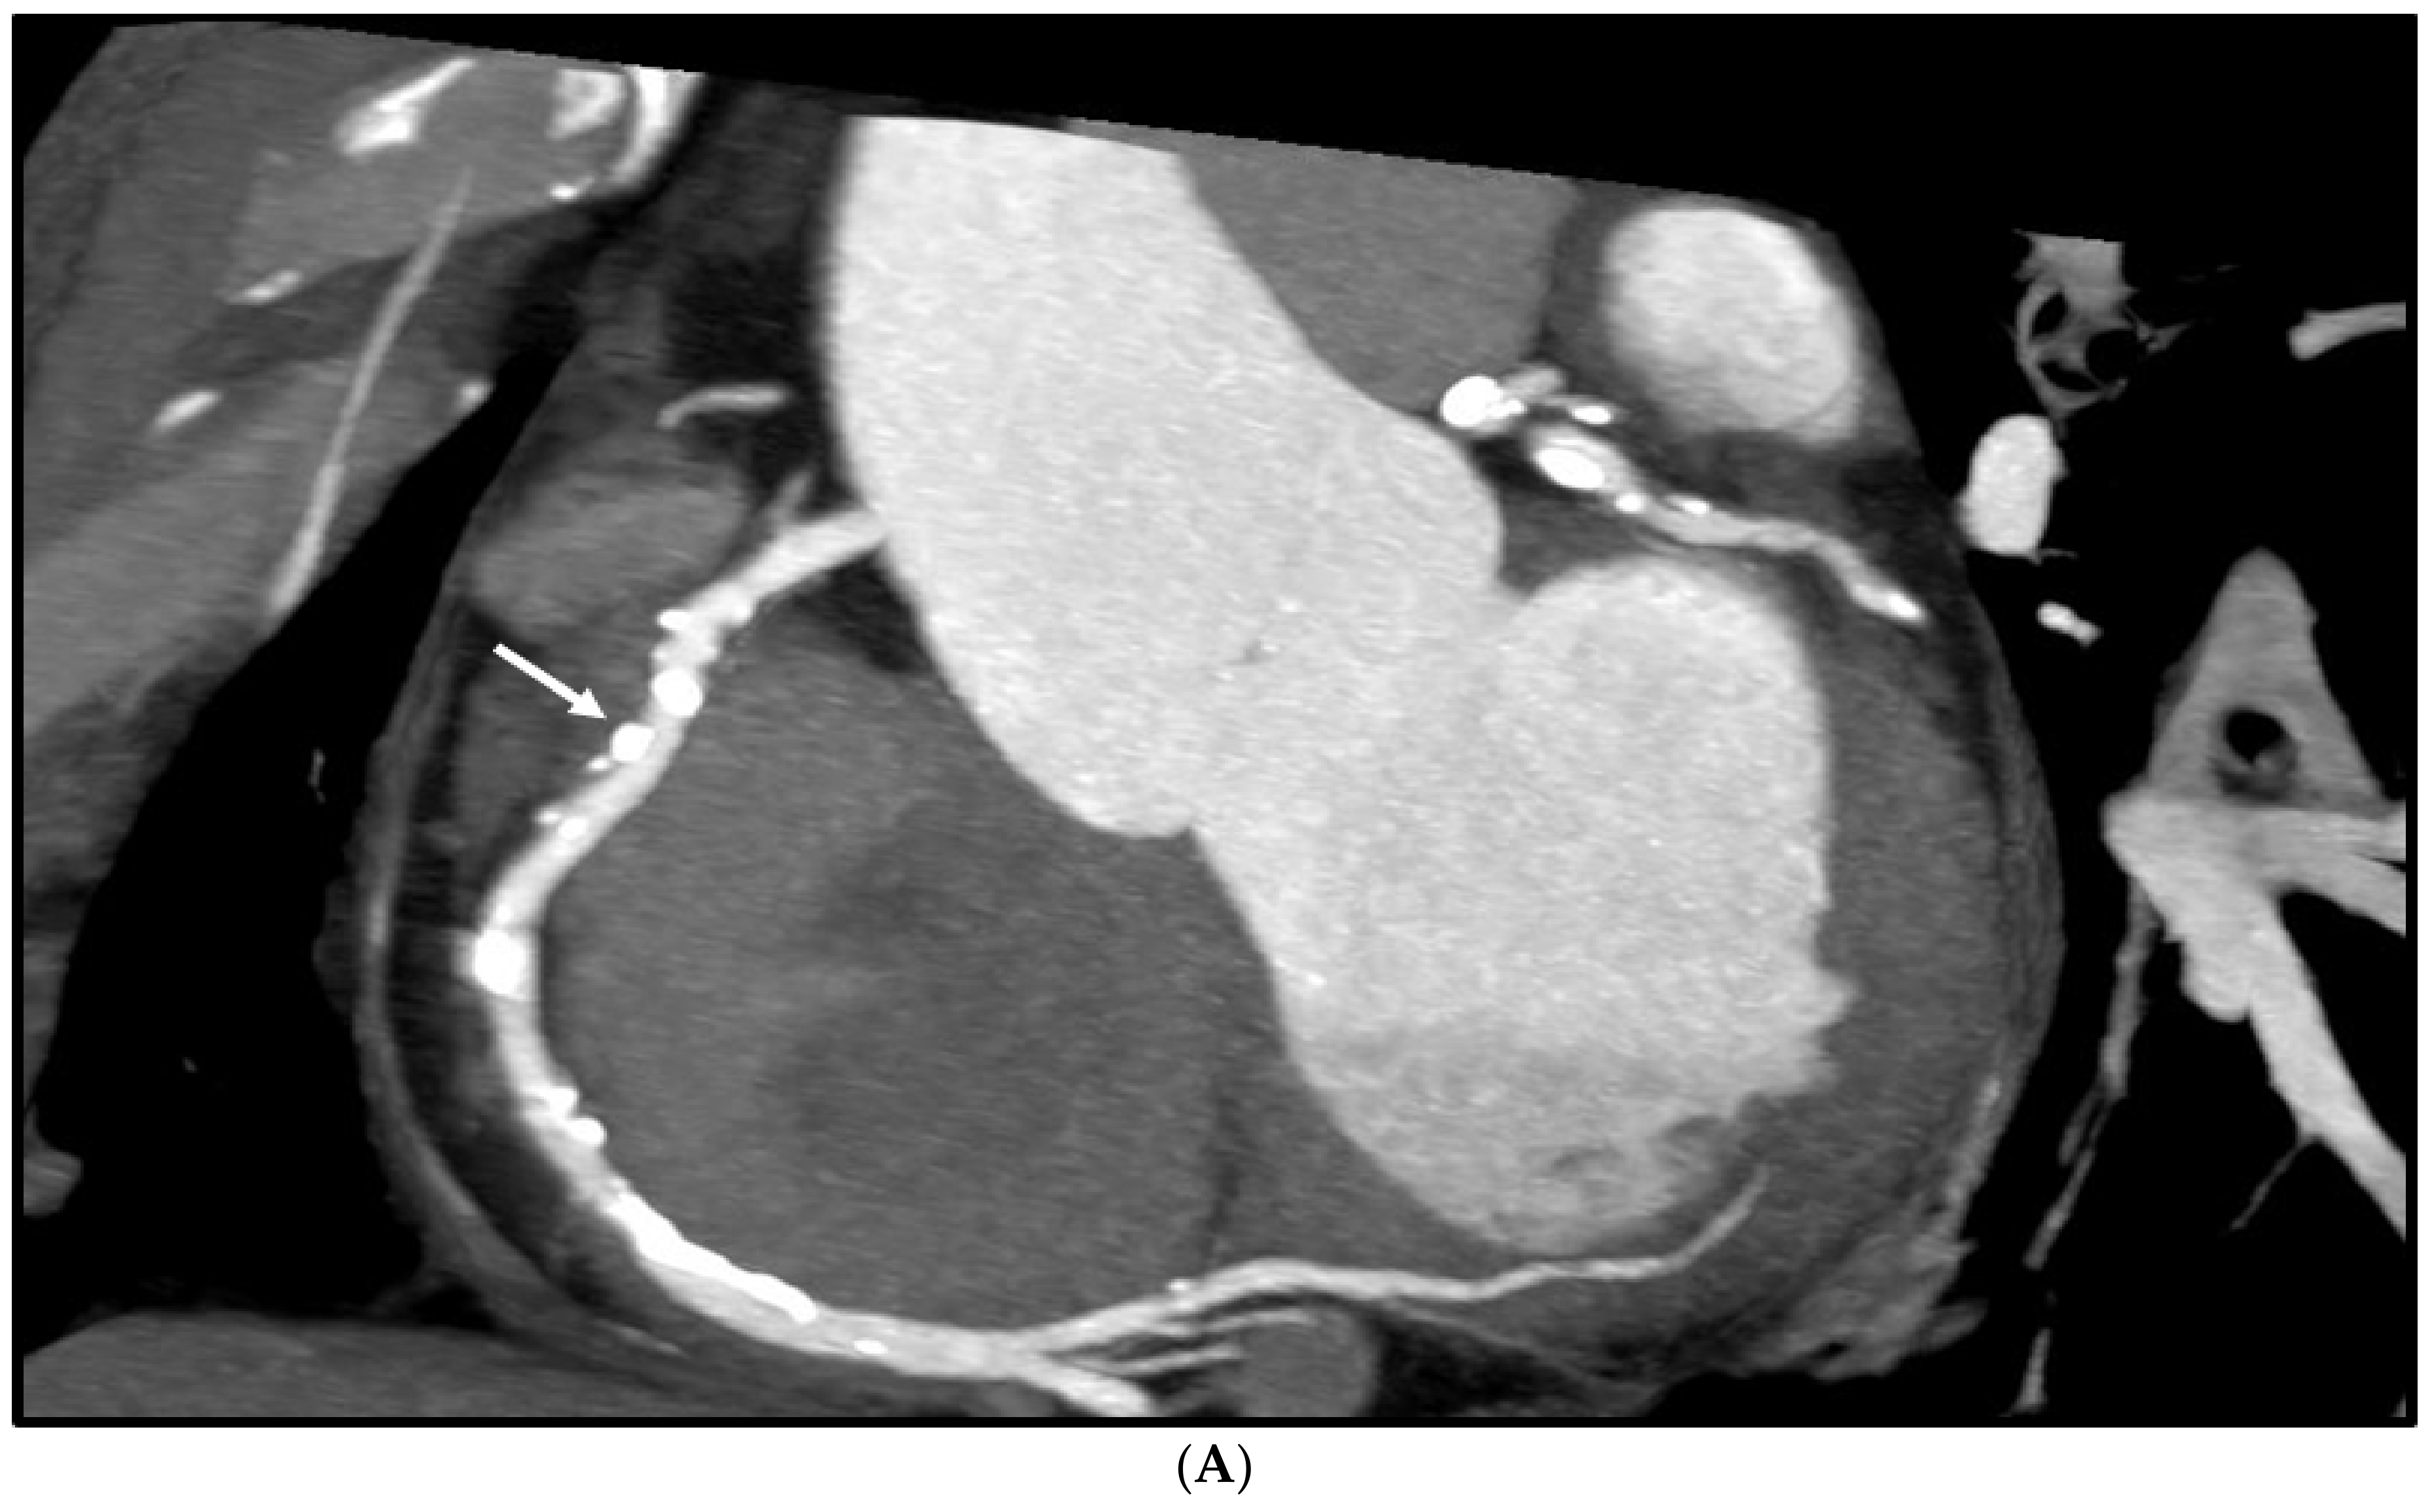

Figure 4 is an example showing multiple calcified plaques at LAD with improvement in the visualisation of coronary lumen observed in ESRGAN-processed images when compared to the original images, while Figure 5 is another example demonstrating multiple calcified plaques at RCA showing improved lumen assessment with ESRGAN-processed images.

Figure 4.

Multiple calcified plaques at the left anterior descending (LAD) artery in a 69-year-old man with coronary artery disease. (A): Comparison of the enhanced super-resolution generative adversarial network (ESRGAN)-processed images with the original coronary computed tomography angiography (CT) image in the assessment of coronary lumen stenosis caused by calcified plaques (arrows), with obvious improvement of lumen assessment, in particular, the ESRGAN-Median (ESRGAN-M) image in the assessment of the first plaque (long arrows). The measured mean stenosis was 63%, 44% and 86% at original CT, 58%, 39% and 83%, 56%, 37% and 83%, and 48%, 36% and 80% corresponding to ESRGAN-High Resolution (ESRGAN-HR), ESRGAN-Average (ESRGAN-A) and ESRGAN-Median (ESRGAN-M) images, respectively. (B): Invasive coronary angiography confirmed no significant stenosis at the LAD with corresponding diameters being 23%, 37% and 28% (arrows), respectively. ESRGAN-M images reduced the false positive rate by 33% when compared to the original CT and other two processed datasets.